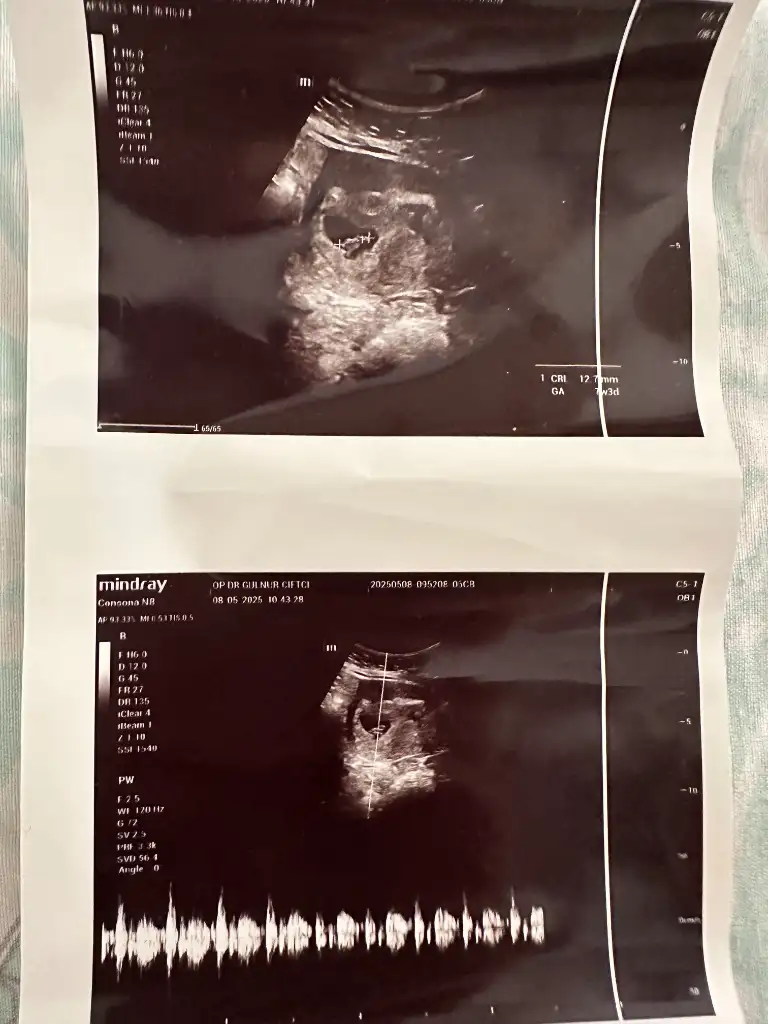

Z zekub Üye Kayıtlı Üye 27 Nisan 2024 236 224 23 24 13 Haziran 2025 Konu Sahibi Konu Sahibi Takitoki #948 8+3 karında ultrason ile çekildi cinsiyet tahmini yapabilecek var mı Eklentiler IMG_20250613_141859.webp 18,6 KB · Görüntüleme: 33